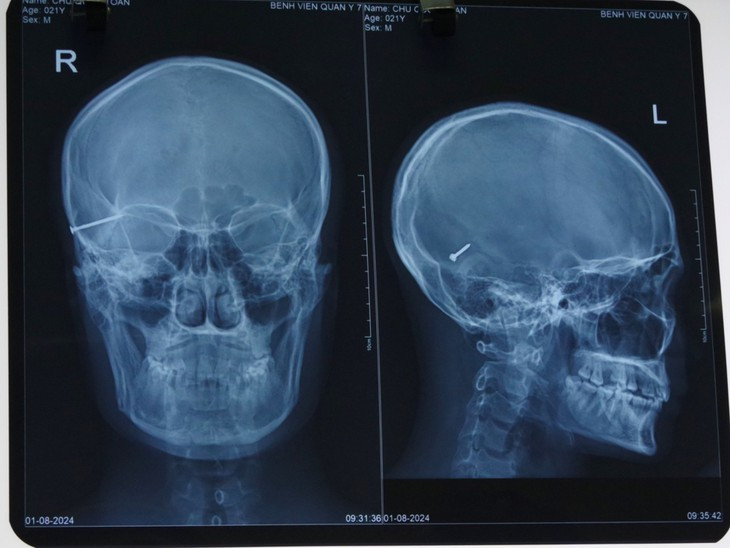

Dị vật kim khí trong sọ bệnh nhân trên phim chụp - Ảnh BVCC

Theo Thượng tá, BSCKII Trần Cao Thượng, Chủ nhiệm Khoa Chấn thương chỉnh hình cho biết: Sau 2 giờ đồng hồ phẫu thuật, dị vật đã được lấy thành công ra khỏi vùng sọ não của bệnh nhân. Đây được xem là một trong những ca mổ khó bởi vì dị vật là một chiếc đinh dài 4cm nằm ở vùng đầu, đòi hỏi trình độ kỹ thuật phức tạp của các y bác sĩ Bệnh viện Quân y 7.